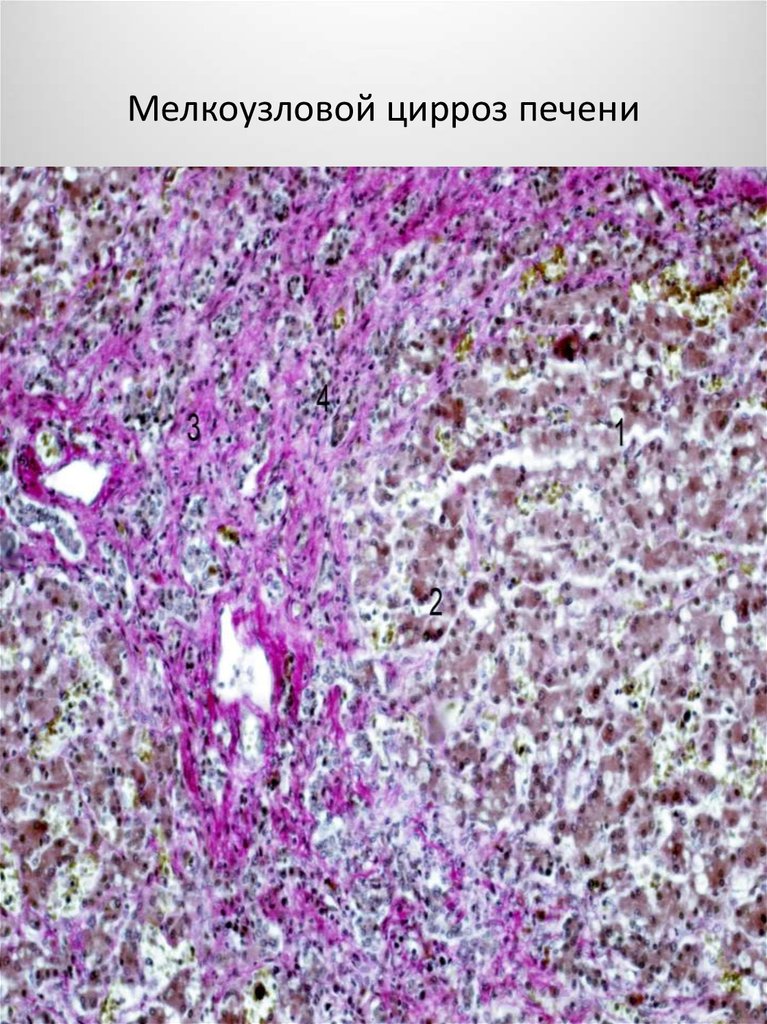

Мелкоузловой цирроз печени